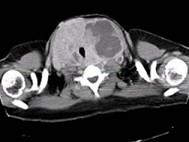

问题 青年女性,咽异物感1年,环状软骨左下方触及一直径2厘米的光滑结节,随吞咽上下活动,生长缓慢,颈部CT检查见下图,患者诊断最可能为 ( )

选项 A、甲状舌骨囊肿 B、颈淋巴结核 C、淋巴结转移癌 D、甲状腺腺廇 E、颈部淋巴瘤

答案 D